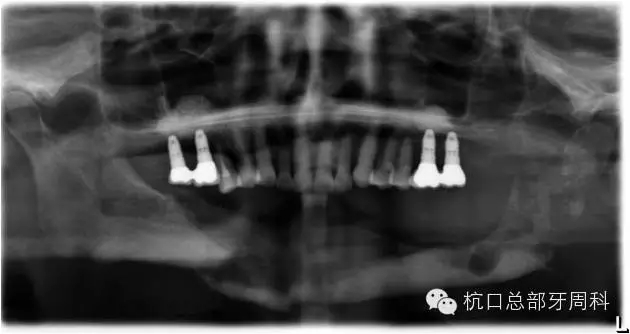

種植后即刻拍片  2005

110.webp.jpg